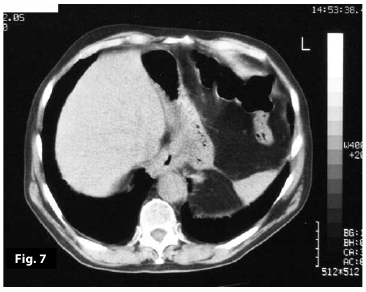

Figure7

Figure8

Figure7-8